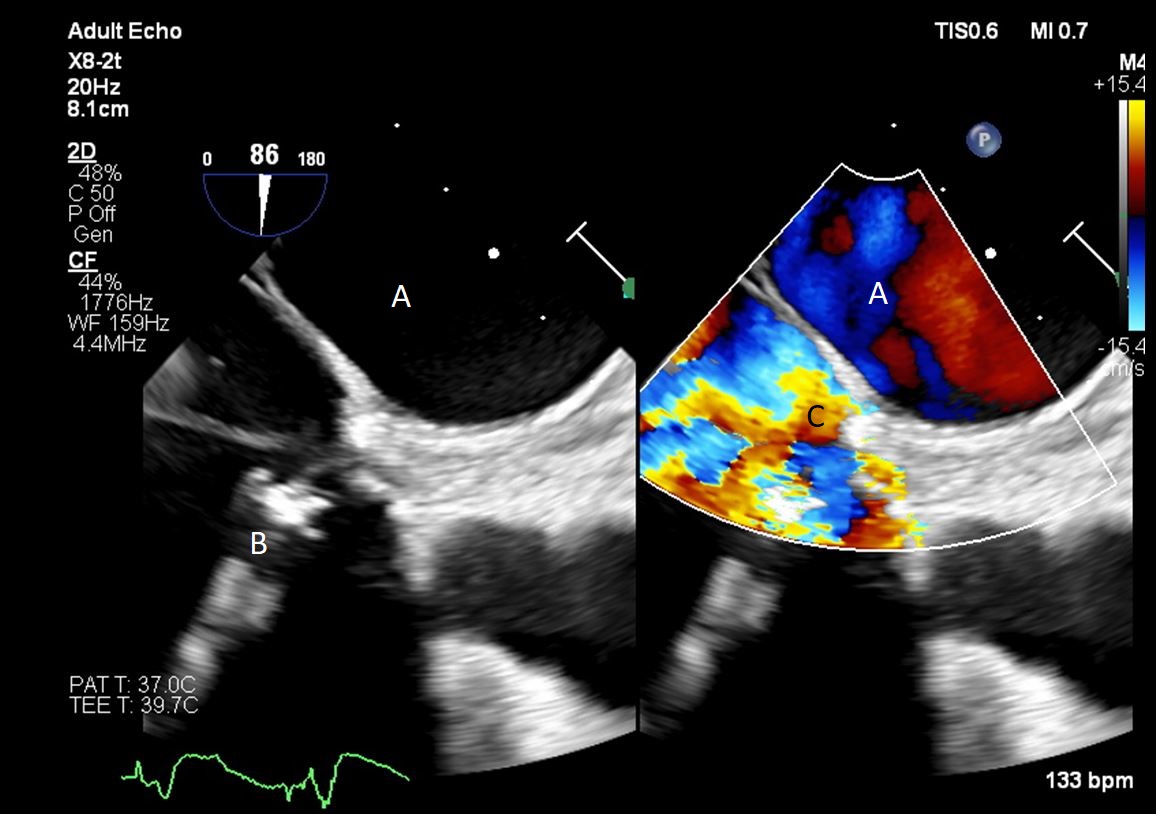

After initial access is obtained with a guidewire, TEE can confirm placement of the guidewire within the aorta and ensure there is no iatrogenic dissection from the procedure. The midesophageal long axis and 4 chamber views can be used to visualize the guidewire crossing of the aortic valve and positioning within the LV cavity. The wire tip should point towards the LV apex. Wire placement too deep within the LV can trigger ventricular arrhythmias and tethering of the mitral valve or subvalvular apparatus should be avoided as this can result in the inlet abutting the mitral valve or damage to subvalvular apparatus (Figs. 3,4) [13]. When the proceduralist is advancing the Impella over the guidewire, the best view to observe the device crossing the aortic valve is the midesophageal long axis view [13].

Impella (A) in the LV cavity caused disruption and damage to subvalvular apparatus resulting in flail segment (B) of the mitral valve.

Fig. 4.Impella (A) placement causing disruption and damage to subvalvular apparatus resulting in mitral valve flail (B) and mitral regurgitation (C).